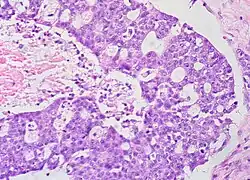

Histopathology

In case an ovarian cyst is surgically removed, a more definite diagnosis can be made by histopathology:

Type Subtype Typical microscopy findings Image

Cystadenoma Serous cystadenoma Cyst lining consisting of a simple epithelium, whose cells may be either:[26]

• columnar and tall and contain cilia, resembling normal tubal epithelium

• cuboidal and have no cilia, resembling ovarian surface epithelium